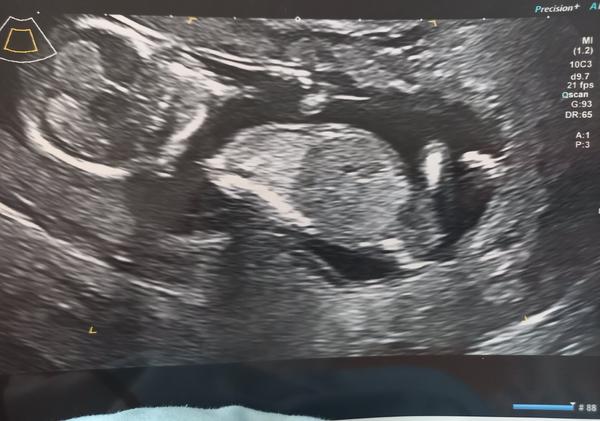

Všichni říkali holku, bylo to velké prekvapko 😂😁😁 taky mam termín v únoru 🙂

@agii1 holčička